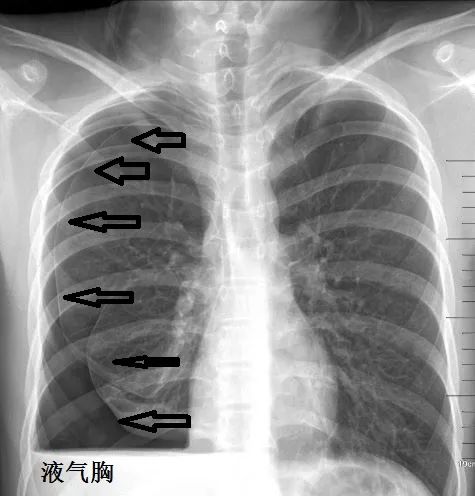

关于流动性差的气胸的X片,先看看慢性不流动气胸,胸片如下:

下面是急性流动性气胸,气往高处走,对比一目了然:

由此可见,对于气胸,CT和X片各有优劣。